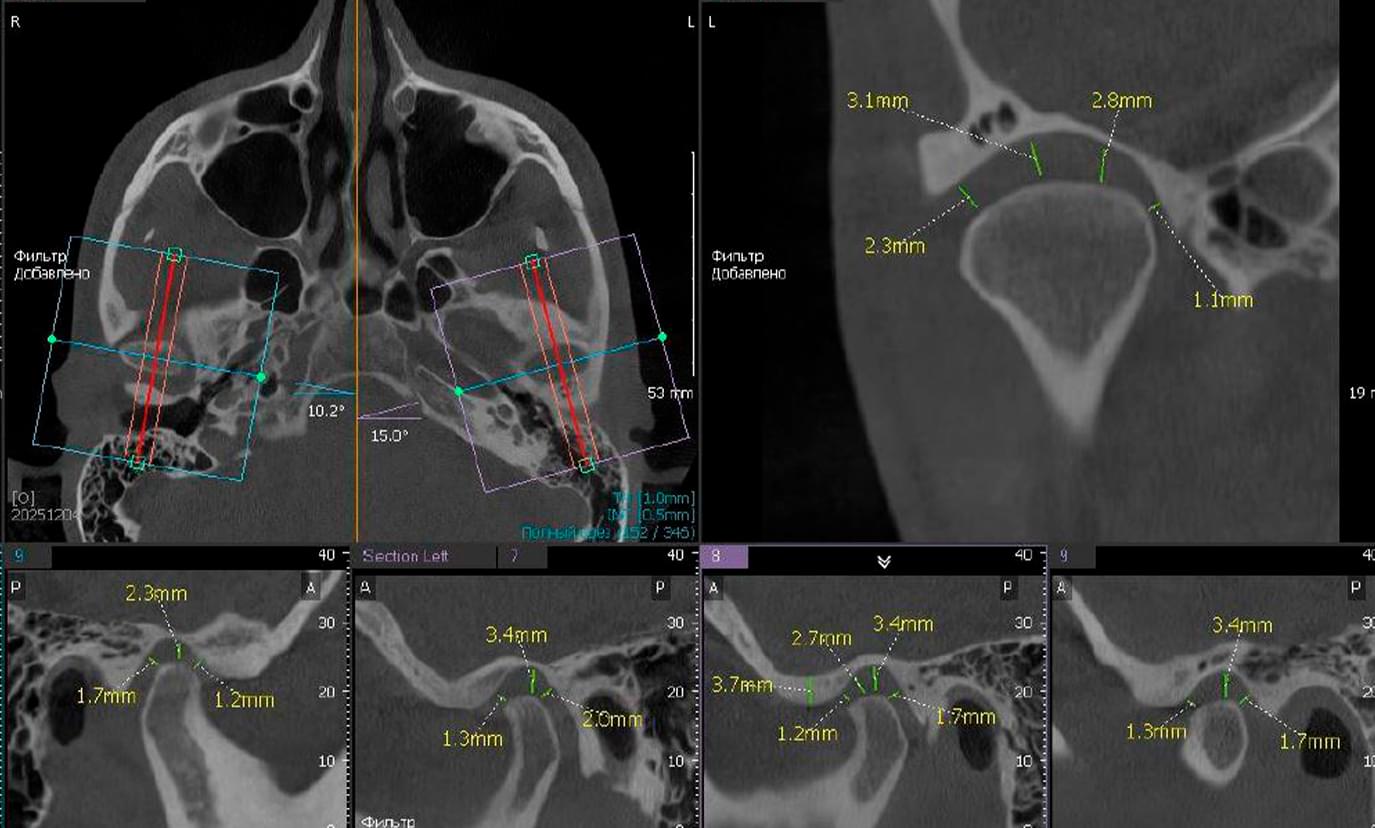

КТ скронево-нижньощелепних суглобів (СНЩС) — це найбільш інформативний метод дослідження рухомого з’єднання нижньої щелепи з черепом. На відміну від плоского панорамного знімка (ОПТГ), 3D-діагностика дозволяє побачити суглоб у стані спокою та при максимальному відкритті рота. Це дає можливість лікарю оцінити не лише структуру кістки, а й ширину суглобової щілини, положення суглобових голівок та симетрію їх руху.

🔹 Положення голівки суглоба: Чи правильно розташована суглобова голівка в ямці при закритому та

відкритому роті (виявлення підвивихів або дислокацій).

🔹 Ширина суглобової щілини: Звуження або розширення простору, що вказує на запальні процеси або

проблеми з диском.